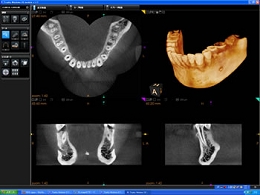

コーンビームCT

・患者様に安心安全なCT

CTとはコンピューター断層撮影装置のことですが、歯の中や骨の中を立体的に撮影し診断を行うための機器です。

インプラント治療はもとより、歯周病の診断、歯の破折、歯内療法における根管の形状や根尖の確認、埋伏歯の位置確認、外科的処置時の動脈や神経の走行状態の診断など、その応用範囲は大変大きく、様々な分野の診査診断において非常に威力を発揮します。

通常の歯科用コーンビームCTは一度に大きな部分を撮影するため、最低でも20秒~40秒以上の撮影時間が必要となるため、被曝線量がどうしても大きくなってしまいます。

当院の歯科用コーンビームCTは顎全体を1/3ずつ分割して撮影することが可能なため、11秒で撮影を完了することができます。このことにより、必要とする部位以外に不必要なX腺を照射する必要がなくなるとともに、被曝腺量を極めて少量に抑えることが可能になります。

現在アメリカなどでは過剰なCT検査による、発癌リスク上昇の危険性が指摘されおりますが、CT大国と言われる日本でも被曝線量を今後十分に考慮する必要があると考えております。